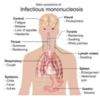

What causes infectious mononucleosis?

EBV infection that results in a lymphocytic leukocytosis comprised of reactive CD8+ T cells (CMV can also cause)

During this, EBV is spread via saliva and primarily infects the oropharynx, resulting in pharyngitis, the liver, resulting in hepatitis with hepatomegaly and elevated LEs, and B cells

Again, in Infectious mono the main immune response is via CD8 T cells, resulting in:

- Generalized LAD due to T-cell hyperplasia in the lymph node paracortex

- Splenomegaly due to T-cell hyperplasia in the PALS

- High WBC count with atypical lymphocytes (reactive CD8 cells) in the blood

How is Infectious mono diagnosed?

Monospot test for screening- detects IgM Abs that cross-react with horse or sheep red blood cells (heterophile Abs). Usually positive 1 week after infection

A negatve monospot test suggests CMV as a possilbe cause of IM

Definitie diangosis made via serologic testing for the EBV viral capsid antigen

What are the complications of infectious mono?

Increased risk of splenic rupture- avoid contact sports

Rash is exposed to ampicillin

Dormancy of vius in B cells elads to increased risk for both recurrence and B-cell lymphoma, especially if immunodeficiency develops